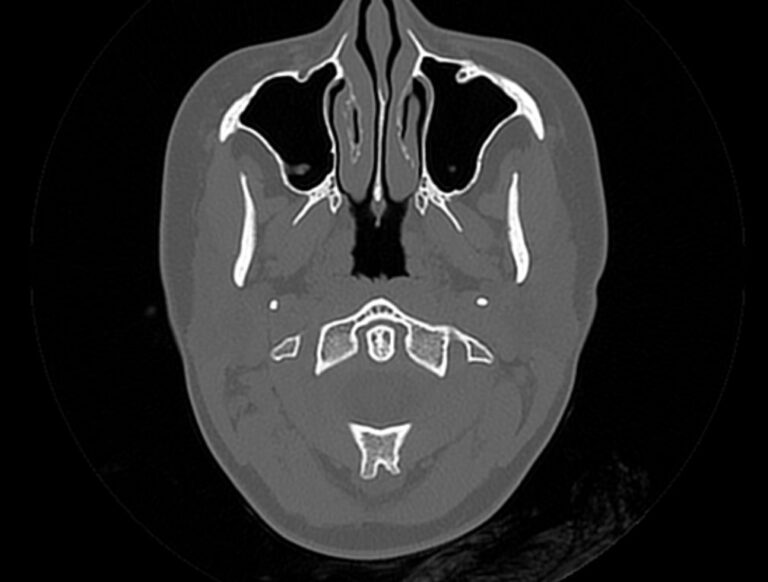

Мультиспиральная компьютерная томография является наилучшим методом диагностики патологии костей черепа. В основе методики лежит использование рентгеновского излучения с последующей цифровой обработкой полученных данных и получения трехмерных реконструкций изображений.

Костная ткань отличается высокой плотностью и способна в большой степени поглощать рентгеновские лучи. Поэтому на послойных снимках, полученных при проведении мультиспиральной КТ черепа можно детально рассмотреть свод черепа, кости лица, основание черепа. Это позволяет с наибольшей точностью визуализировать различные объемные образования, такие как остеомы, дифференцировать фиброзную дисплазию или костные метастазы. Преимуществами методики КТ является отличная визуализация костных структур, быстрота выполнения процедуры и доступная цена. Все это делает КТ незаменимой при диагностике травматических повреждений (например переломов основания черепа или орбит), аномалий развития, при планировании оперативных вмешательств.